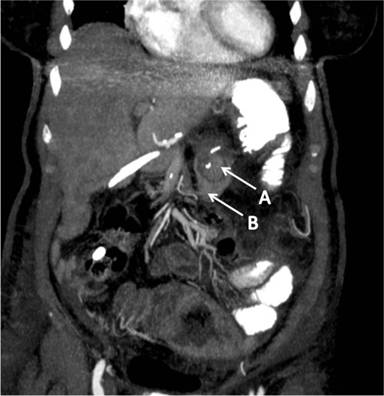

We would like to share with the readers interesting computerized tomography (CT) images of a pancreaticojejunostomy fashioned by a telescopic invagination anastomosis between the remnant of the pancreas and a loop of the small bowel.

Image 2 presents a sagittal view of the pancreaticojejunostomy, with the pancreatic stump (A) invaginated with the bowel loop (B) and its mesentery.

Image 2 |